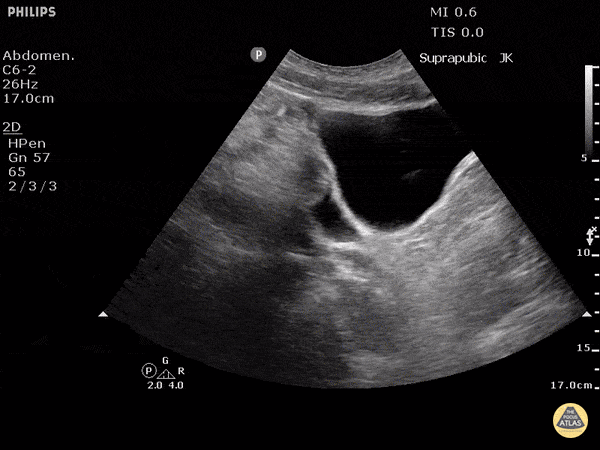

Trauma - Positive FAST - Pelvis - Sagittal

Blunt trauma patient with POSITIVE FAST scan. Free fluid can be seen posterior to the dome of bladder in this sagittal view. Dr. Justin Bowra